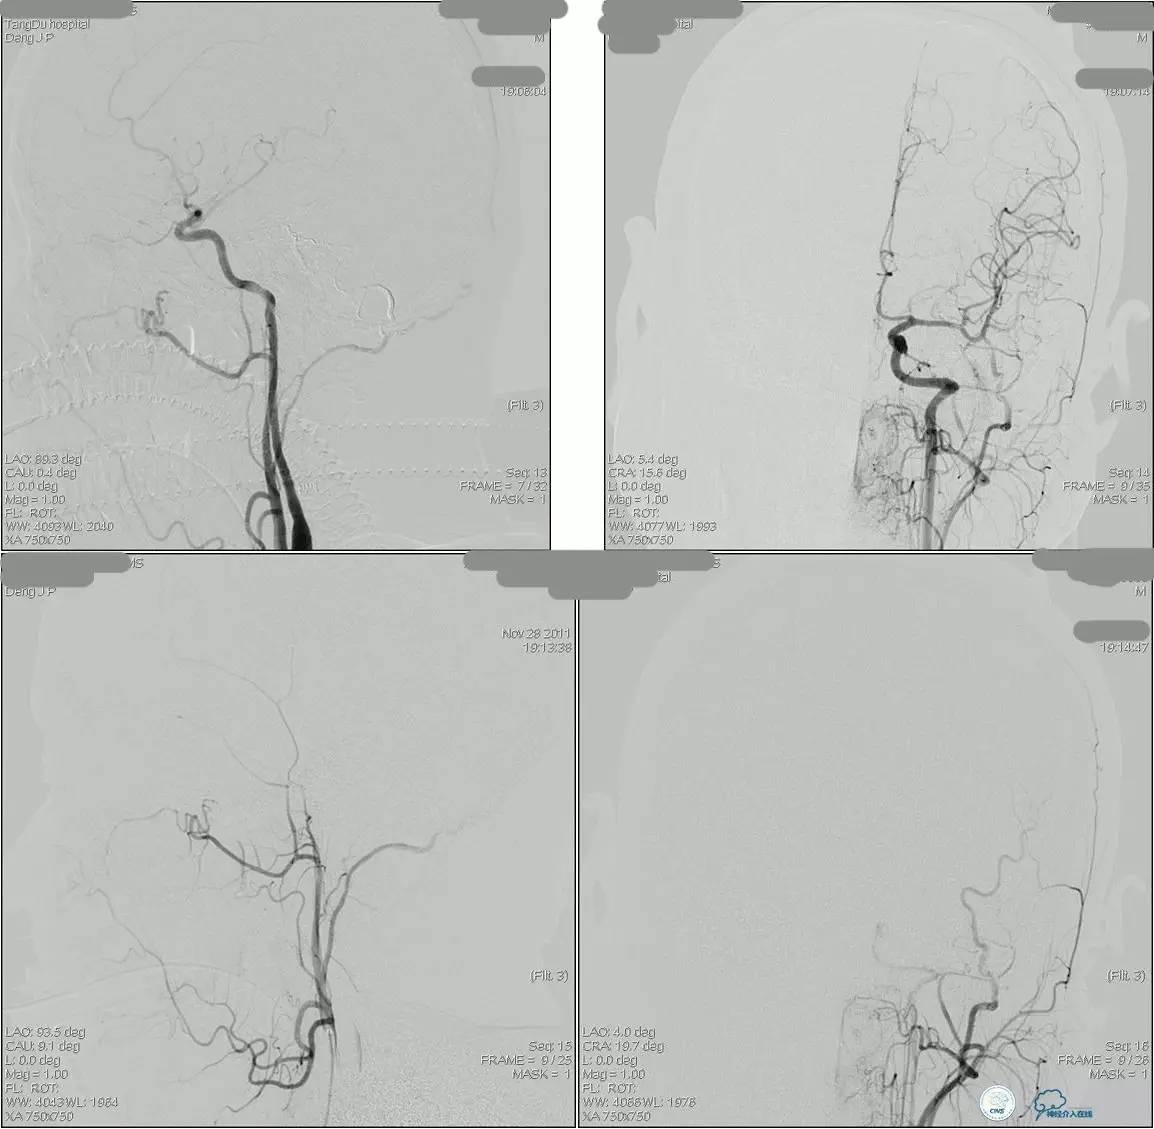

海绵窦区DAVF,颈内外均参与供血。

采用净买入路,经岩下窦栓塞。

首先放入少量弹簧圈,给Onyx提供框架。

开始注入Onyx时,在颈内动脉内放入保护球囊,防止意外进入颈内动脉内。

栓塞后胶的透视影像。

最终结果,DAVF完全消失。

侧窦区DAVF,直接引流入横窦,为保护窦,横窦放入球囊8*80。

最终栓塞结果,窦通畅。